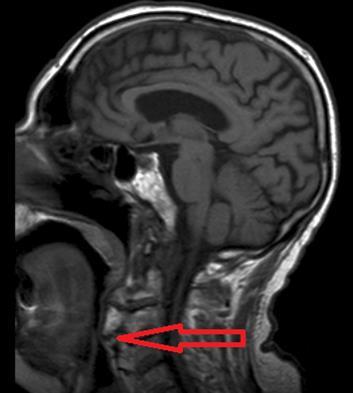

Brain and cervical MRI were performed to exclude recent brain ischemic lesions and to investigate the spinal chord involvement in relation to the known severe osteophytosis. The brain MRI showed only signs of chronic vasculopathy and no images related to acute events. The neck MRI revealed no medullary compression or signal alterations; osteophytes originating from C1 to C7 were described and had a compressive and displacing effect on the upper aero-digestive ways and laryngeal post-cricoid area. Osteophytes were forming bony bridges in the anterior prevertebral space from C3 to C7.

Figure 1.Osteophytes-induced upper airways obstruction